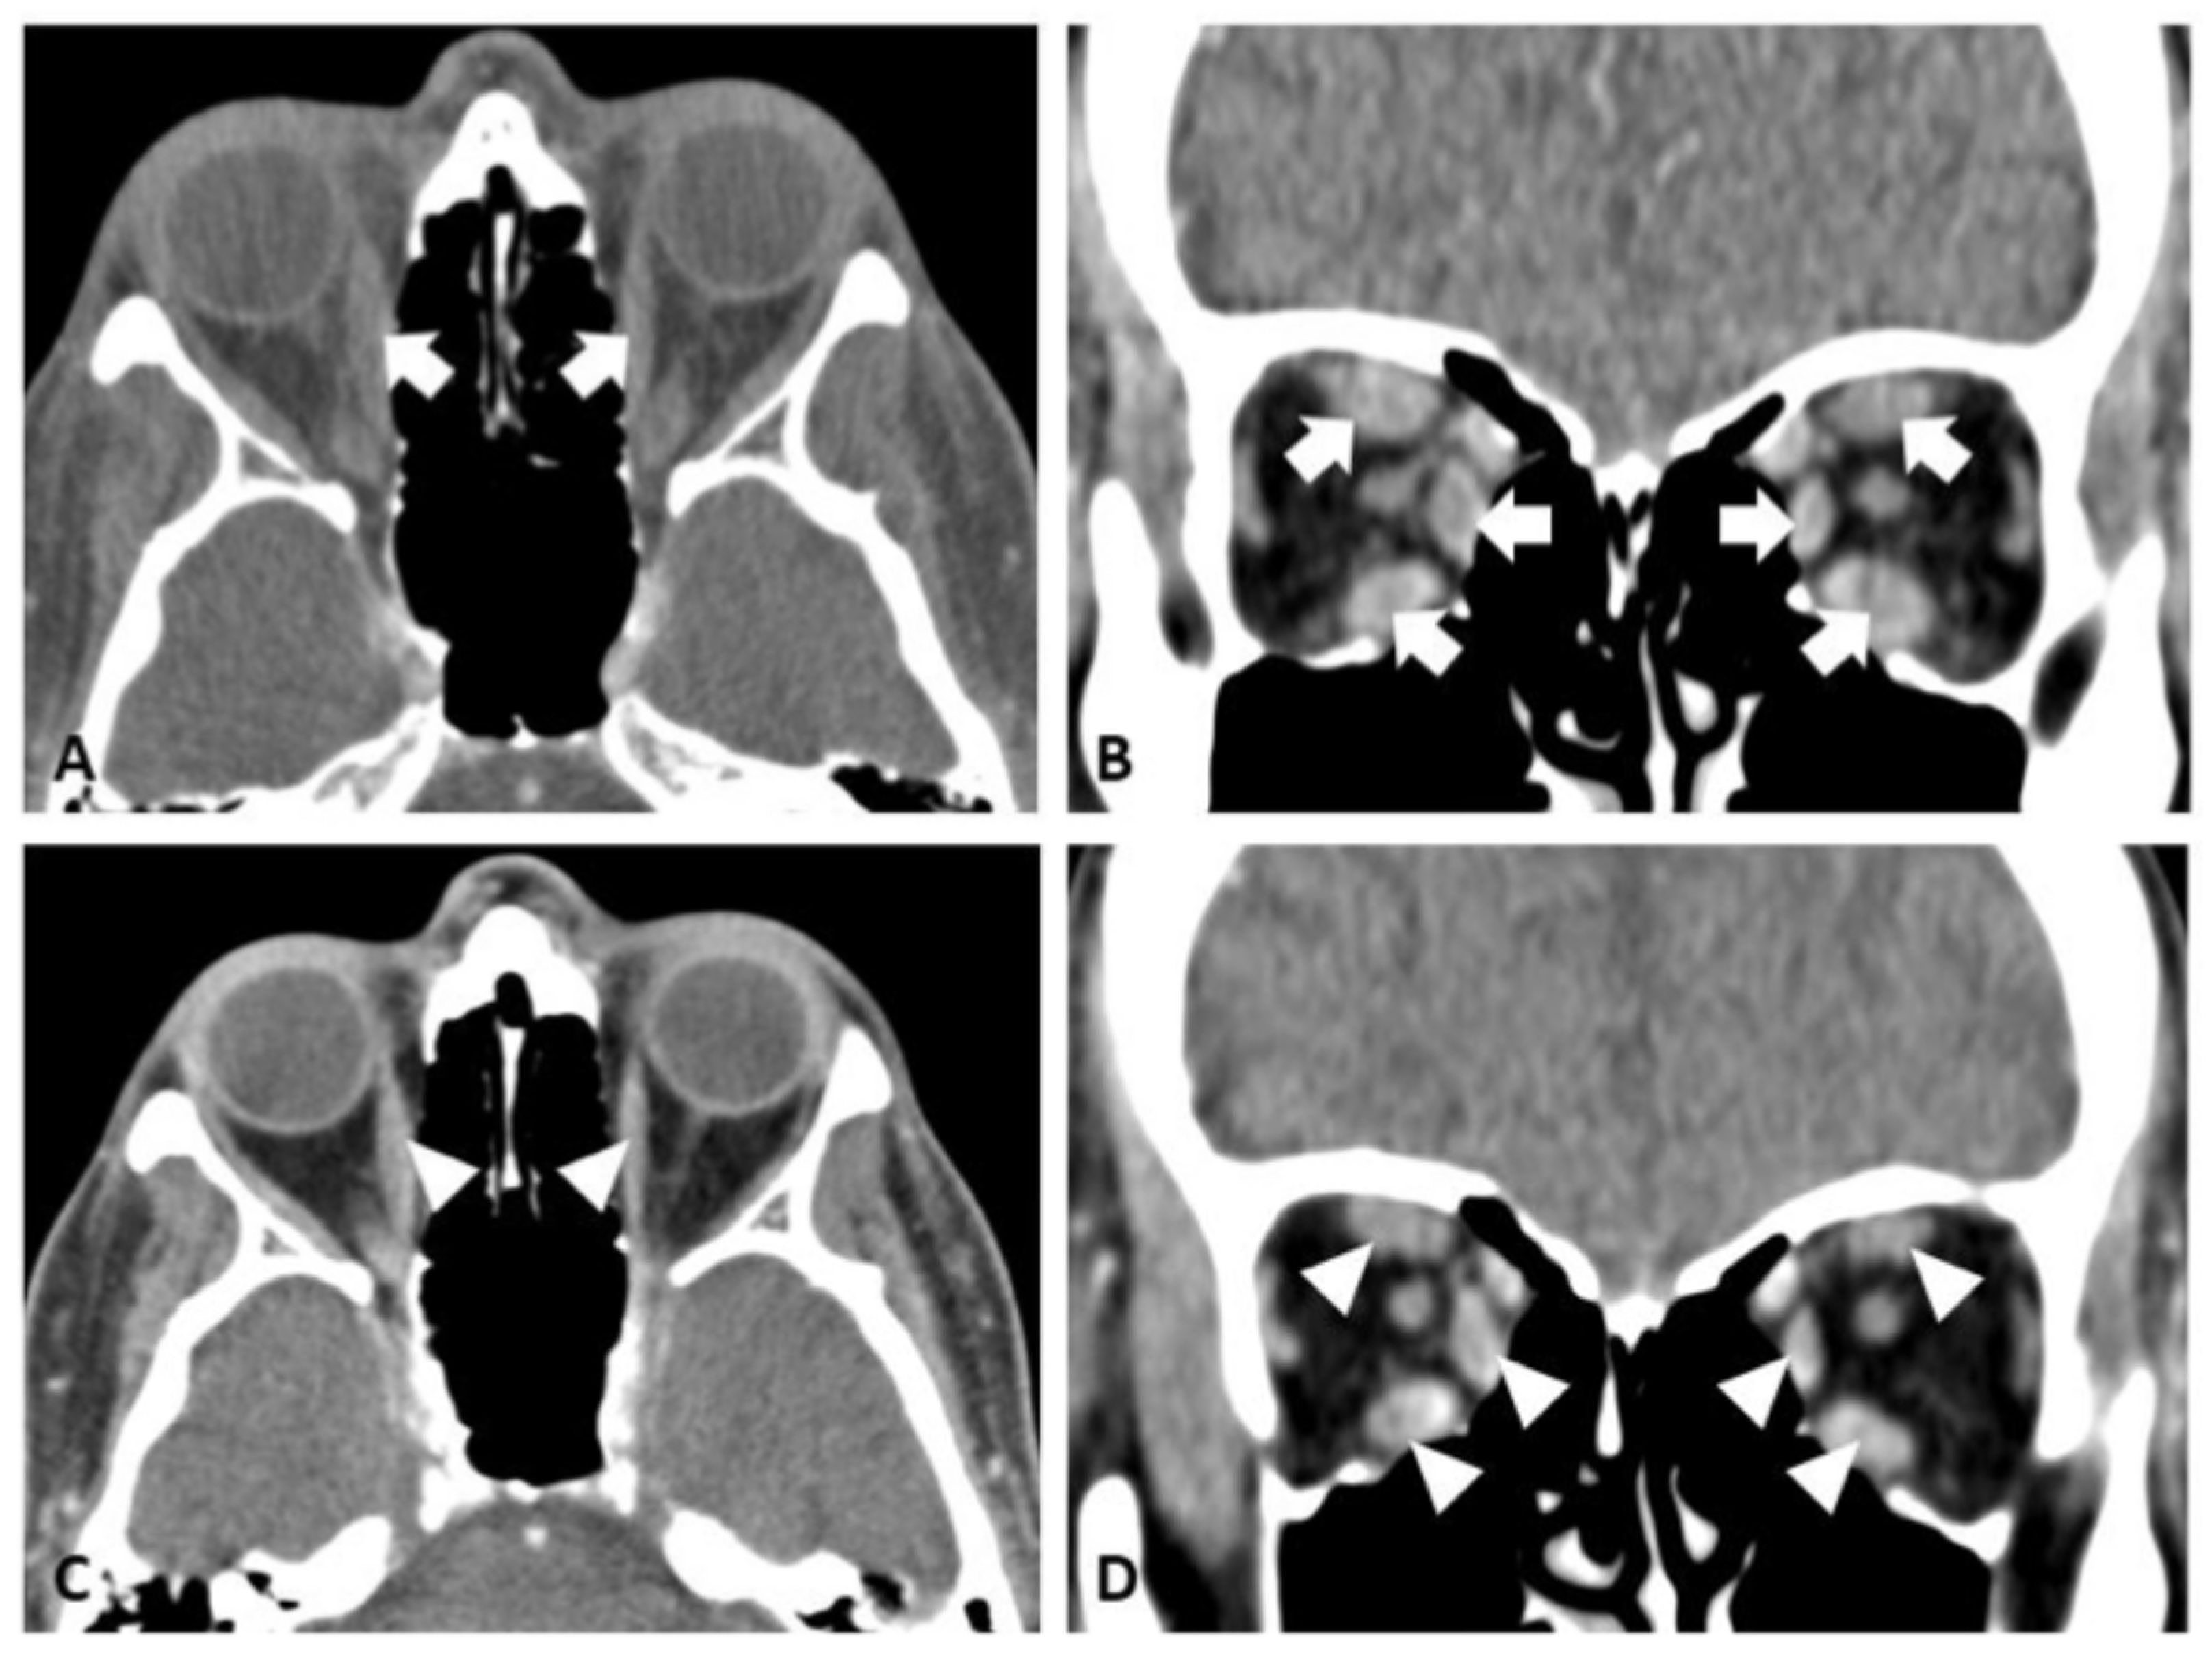

2.1. Case 1

2.2. Case 2